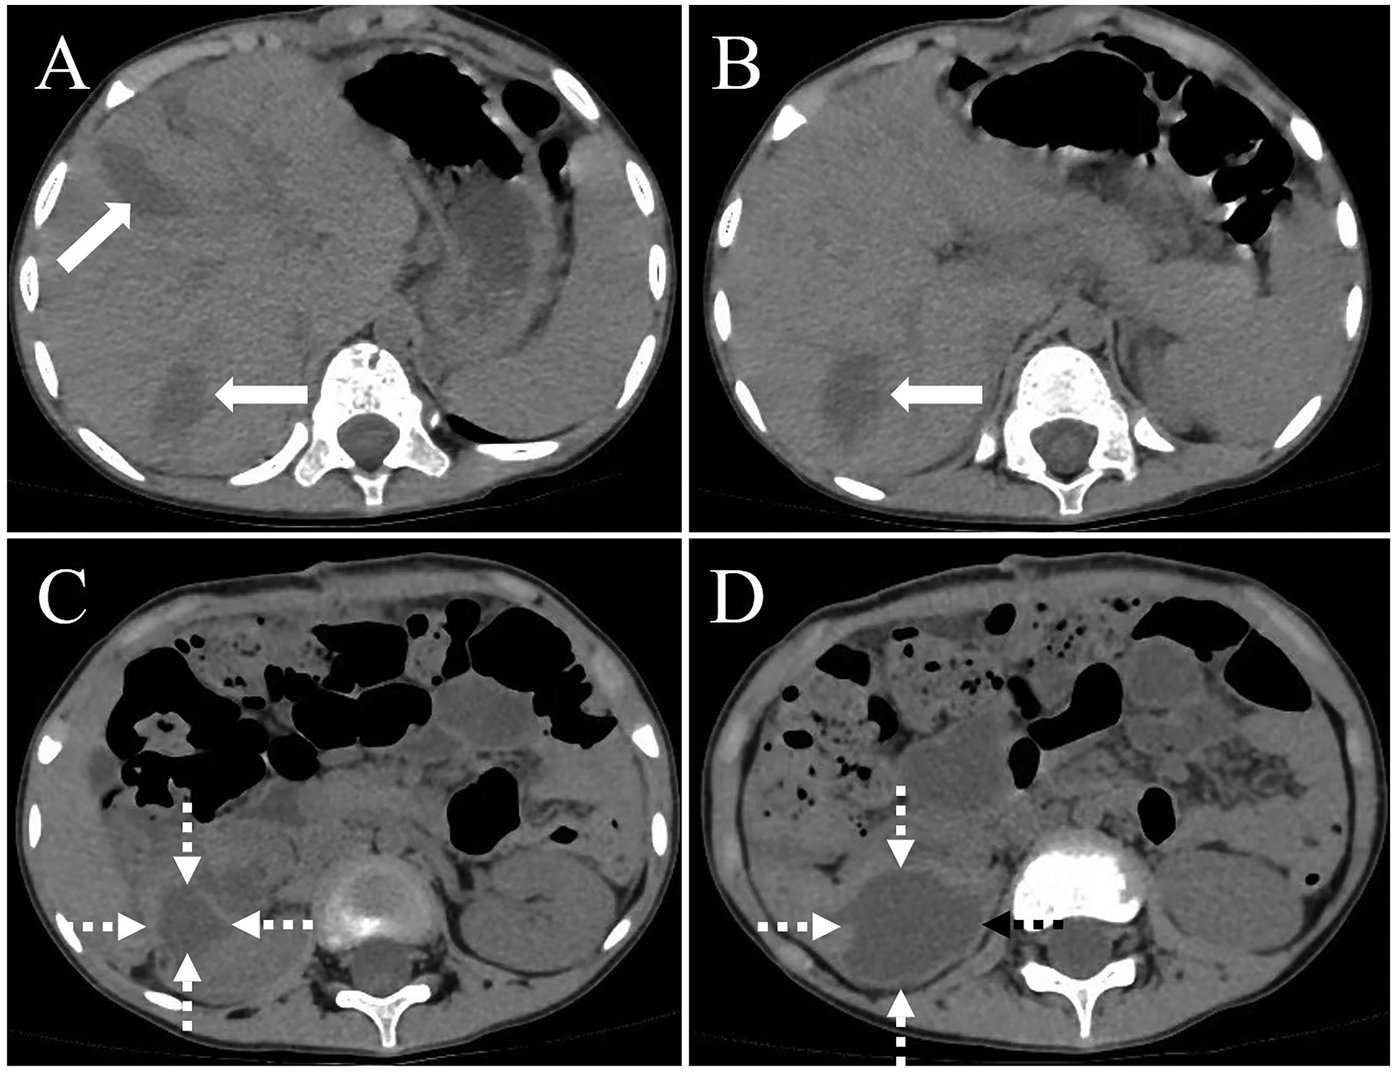

On February 10, 2025, a 5-year-old boy from a rural region of Tibet, China, where yak herding constitutes the predominant economic activity, was admitted to the hospital following the identification of a palpable abdominal mass one month prior. The mass, situated in the right lower quadrant of the abdomen, measured approximately 5 cm in diameter and exhibited a slightly firm consistency. The patient exhibited no symptoms of nausea, vomiting, abdominal pain, or other gastrointestinal disturbances. Furthermore, there were no indications of jaundice or superficial lymphadenopathy. His medical history was unremarkable, and there was no reported family history of echinococcosis. Laboratory investigations revealed a normal complete blood count and liver function tests. However, enzyme-linked immunosorbent assay (ELISA) testing revealed the presence of specific IgG antibodies in the serum. Computed tomography (Figure 1) demonstrated multiple hypodense lesions distributed throughout the liver, with the largest lesion in the posterior segment of the right lobe measuring approximately 72 × 55 mm, which did not exhibit enhancement on contrast imaging. The inferior vena cava exhibited compression and narrowing, accompanied by partial occlusion of the right kidney. Based on the imaging and serological assessments, a preliminary diagnosis of complex hepatic echinococcosis and renal cyst was established. A comprehensive multidisciplinary team (MDT) discussion was conducted, involving pediatricians, anesthesiologists, urologists, and infectious disease specialists. The following considerations were made: (1) Infectious Disease Department: Due to the patient's young age, prolonged disease duration, and the substantial size of the parasitic cysts, oral albendazole was deemed to have limited efficacy and posed significant potential side effects. Consequently, surgical intervention was prioritized. (2) Hepatobiliary Surgery: The patient presented with multiple hepatic lesions. To achieve radical treatment, pericystectomy was identified as the preferred surgical approach. Despite the patient's classification as Child-Pugh A in terms of preoperative liver function, hepatic inflow occlusion was avoided during surgery to preserve liver function, given the patient's young age. (3) Urology: The preoperative assessment of the renal cystic lesion presented challenges in accurately determining its nature. The differential diagnoses considered included a simple cyst, hydronephrosis, and renal echinococcosis. In the event that a simple renal cyst was identified intraoperatively, the planned intervention involved cyst puncture and drainage. Conversely, if an echinococcal infection of the right kidney was confirmed, the strategy to preserve renal function prioritized endocystectomy, while nephrectomy was not contemplated. (4) Anesthesiology: The intraoperative anesthesia management strategy focused on maintaining central venous pressure (CVP) above 5 cm H₂O, with the objective of mitigating hepatic ischemia-reperfusion injury. (5) Postoperative Care: The patient was scheduled for transfer to the pediatric intensive care unit to facilitate close monitoring of liver function and to prevent potential complications. Under general anesthesia, the patient underwent a radical multiple pericystectomy of the liver, in conjunction with an endocystectomy of a right renal hydatid cyst, as well as biliary repair and reconstruction (Figure 2). Intraoperative exploration revealed multiple firm, translucent masses located in segments II, III, IV, and VII of the liver, each encapsulated by intact cyst membranes. These masses were found to be closely adherent to the first and second hepatic portal veins, with the inferior vena cava observed to be compressed and narrowed. Additionally, multiple small nodules were noted protruding from the liver surface; however, the diaphragm remained uninvolved. Upon resection and incision of the masses, the contents were identified as powdery, skin-like tissue and brownish-yellow fluid, which communicated with the biliary tract. No nodules were detected in the omentum, abdominal wall, or intestines, and there was an absence of ascites. A large cystic, translucent mass was also identified in the right kidney, which was poorly demarcated from the surrounding renal tissue. Histopathological examination confirmed infection with Echinococcus granulosus (Figure 3). In the postoperative period, the patient experienced transient hypernatremia (sodium 165.7 mmol/L) and hepatic dysfunction. Hepatoprotective therapy was initiated, and hypernatremia was effectively managed through the administration of a 5% glucose solution and furosemide. Subsequently, the patient underwent treatment with albendazole (100 mg per dose, administered twice daily) and exhibited a favorable recovery trajectory. At the one-month postoperative follow-up, the patient presented with no signs of jaundice in the skin or sclera. The abdominal examination revealed a soft abdomen without tenderness. Laboratory evaluations, including liver and kidney function tests and complete blood cell counts, were within normal limits. An abdominal CT scan showed no evidence of echinococcosis recurrence (Figure 4).

Figure 1

Preoperative computed tomography (CT) findings. (A) CT imaging of the hepatic hilum region shows hypodense masses in liver segments 2, 3, 4, and 7 (arrows). (B) CT examination of the first hepatic portal region reveals multiple large cystic lesions within the liver (arrows). (C) A large cystic lesion is observed in the right kidney (dashed arrow), with the largest cross-sectional area measuring approximately 11.3 × 8.9 cm, and focal discontinuity is noted in the right kidney. (D) Pelvic CT scan demonstrates a large cystic lesion originating from the right kidney (dashed arrow).